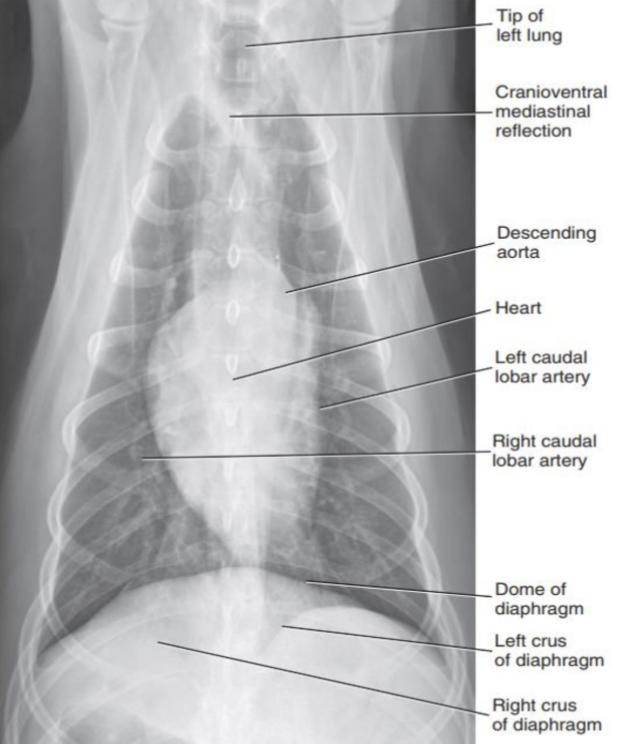

1. Normal Anatomy

| 정상적인 공기의 흐름 : Trachea - Bronchus - Bronchioles - Lung |